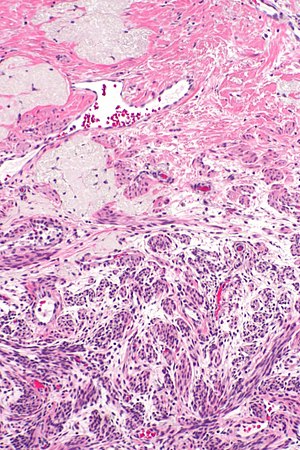

Ablated_endometrium. H&E stain. | |

| LM | endometrium completely or partially replaced by hyaline material and fibrosis |

- Endometrium completely or partially replaced by:

- Hyaline material, fibrosis.

UTERUS, UTERINE CERVIX, TOTAL HYSTERECTOMY: - SUPERFICIAL FIBROSIS AND HYALINE CHANGE OF THE UTERINE LINING -- COMPATIBLE WITH PRIOR ABLATION. - UTERUS WITH LEIOMYOMAS. - UTERINE CERVIX WITHIN NORMAL LIMITS.